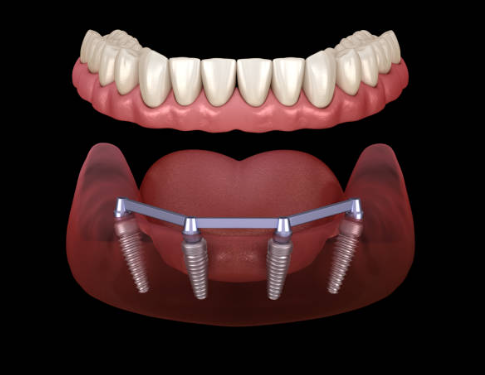

임플란트는 크게 세 부분으로 나뉘며, 치아 뿌리를 대신하는 구조물인 임플란트 (인공치근), 그 위에 체결을 하는 보철기둥 (지대주), 마지막으로 그 위에 씌우는 보철물 (크라운)이 있습니다.